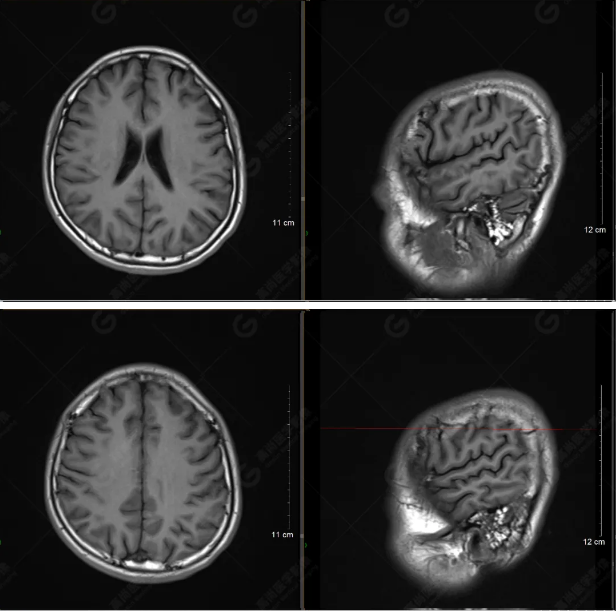

(左側(cè)為薄層原始圖像,右側(cè)為后處理5mm圖像)

SWI序列影像表現(xiàn)及診斷

左側(cè)額底及左側(cè)顳葉內(nèi)見多發(fā)斑點狀極低信號影??紤]額顳葉多發(fā)腦挫傷伴微出血、含鐵血黃素沉著,左側(cè)乳突骨折、乳突內(nèi)積血。討論:1、SWI利用不同組織間磁敏感的差異成像并將其放大,通過檢測病灶中的靜脈分布、出血灶和礦物質(zhì)沉積等,有效改善了相關(guān)疾病的診斷,主要應(yīng)用于中樞神經(jīng)系統(tǒng)。2、根據(jù)磁距圖像和相位圖像表現(xiàn),對于鑒別顱內(nèi)出血及鈣化有一定程度的價值,用于彌補(bǔ)MRI對鈣化顯示的不足。